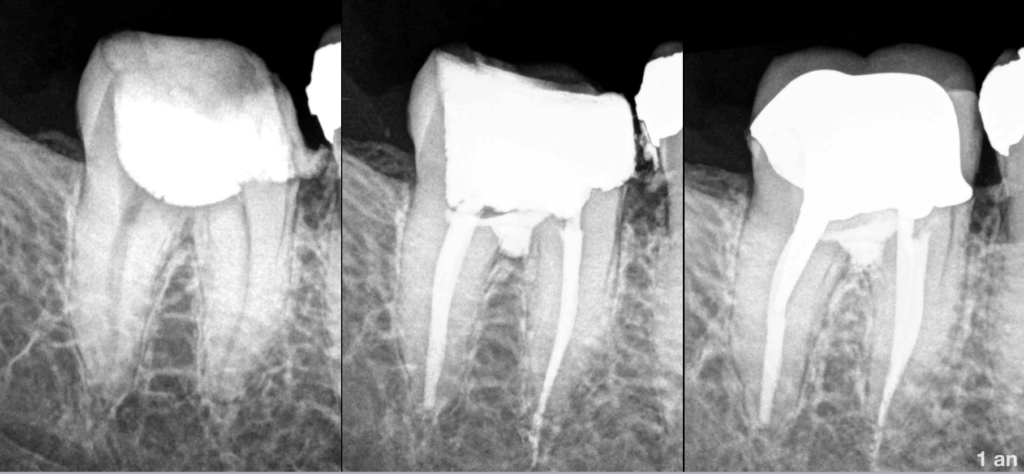

- Traitement précédemment initié

- 𝐎𝐬 𝐩𝐞́𝐫𝐢–𝐚𝐩𝐢𝐜𝐚𝐥 𝐧𝐨𝐫𝐦𝐚𝐥

- Perforation de la furcation.

𝐓𝐫𝐚𝐢𝐭𝐞𝐦𝐞𝐧𝐭 𝐜𝐚𝐧𝐚𝐥𝐚𝐢𝐫𝐞 + traitement de la perforation.